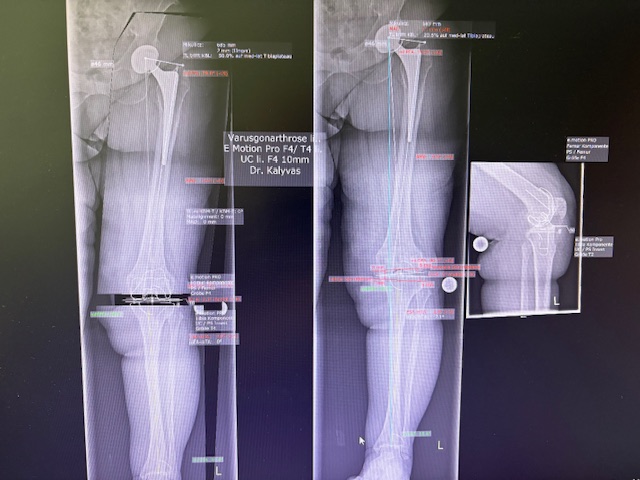

Ο προεγχειρητικός ψηφιακός σχεδιασμός

Πραγματοποιήθηκε σε ειδική ακτινογραφία ολόκληρων των δύο κάτω άκρων. Σε αυτό το ψηφιακό μοντέλο σχεδιάστηκε με ακρίβεια το είδος, το μέγεθος και η ακριβής θέση των προθέσεων, με βάση τα ανατομικά χαρακτηριστικά της ασθενούς.

Ο ψηφιακός σχεδιασμός επιτρέπει απόλυτη εφαρμογή των μοσχευμάτων, ελαχιστοποιώντας τα περιθώρια απόκλισης και εξασφαλίζοντας άριστη ευθυγράμμιση και κινηματική ισορροπία του γόνατος.

Τα εμφυτεύματα που χρησιμοποιήθηκαν στο γόνατο της ασθενούς είναι της Aesculap: E-Motion Pro, μηριαίο μέγεθος 4, κνημιαίο μέγεθος 4, με ενθέμα (inlay) 10mm.